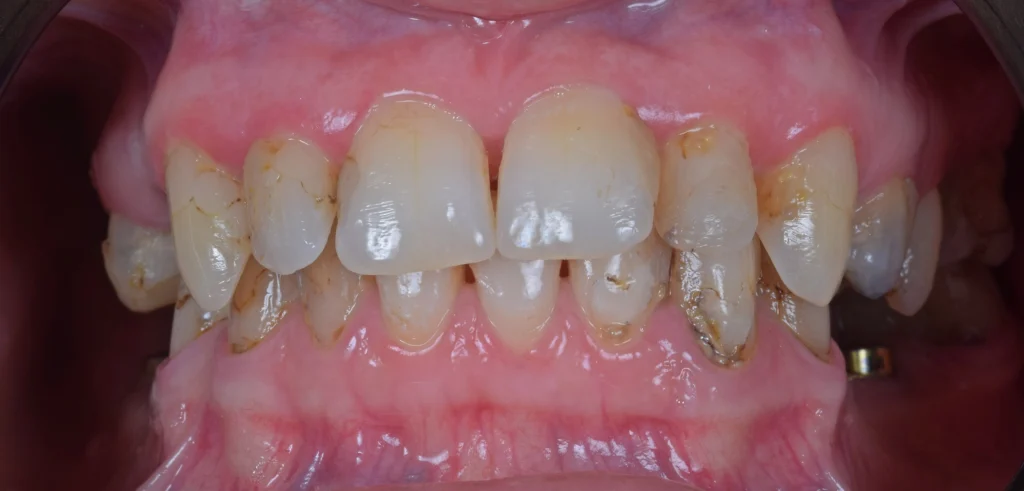

This lovely patient came to our clinic with several missing teeth and a misaligned bite, which significantly affected both her oral health and self-confidence. Everyday activities such as eating and smiling had become a challenge, impacting her overall quality of life.

After a thorough clinical examination and advanced 3D CBCT imaging, we carefully analyzed her condition and created a fully personalized treatment plan.